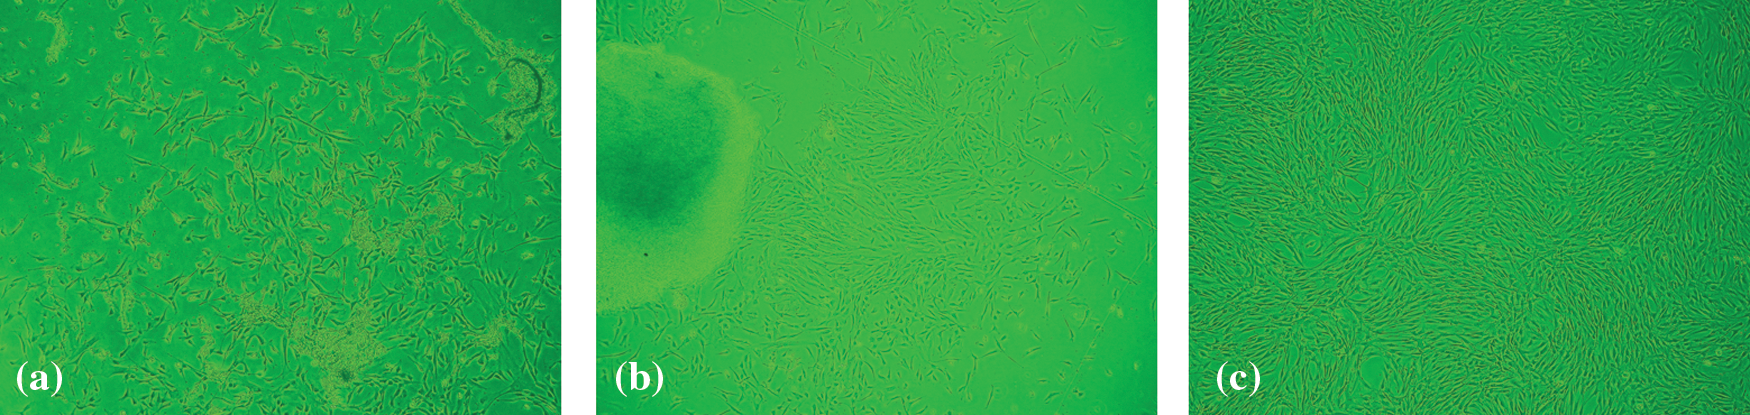

Observation by inverted phase-contrast microscopy

Only spindle-shaped cells were present in the culture. The proportion of the nucleus and cytoplasm was large. The adherent cells’ growth is shown in Figs. 1A–1C. To observe the three kinds of MSCs on morphological characteristics, the cell morphology was observed under an inverted microscope on the 14th day. All the three kings of cells grew adherently and spirally. The third passages of the three kinds of MSCs were used. Because the third generation MSC of placenta mesenchymal has the strongest differentiation ability with more activity. All the following experiments used third-generation placental MSCs.

Figure 1: Morphological characteristics and the cell morphology of three sources of mesenchymal stem cells. (a) Umbilical cord blood mesenchymal stem cell. (b) Umbilical cord mesenchymal stem cell. (c) Placenta mesenchymal stem cell